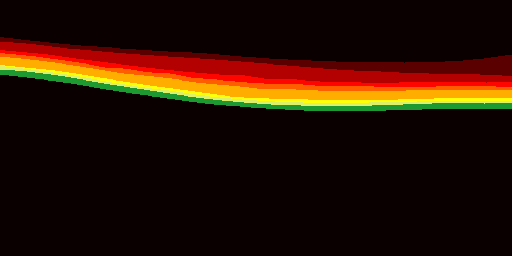

One of Mind+’s recent goals is to develop efficient and accurate Optical Coherence Tomography (OCT) image segmentation and classification algorithms to provide better diagnostic and treatment support for ophthalmologists. We will leverage the most advanced artificial intelligence technology and medical image analysis expertise to continuously optimize our algorithms and improve the accuracy and efficiency of diagnoses.

At the same time, we will work closely with ophthalmology healthcare institutions and experts to understand their needs and feedback, ensuring that our algorithms can meet the practical application scenarios and requirements of our customers. We believe that through our efforts, we can bring more efficient, accurate, and reliable services and support to the ophthalmology healthcare industry.

We are confident that this work will have a significant impact on ophthalmology healthcare, helping doctors diagnose and treat eye diseases more quickly and accurately, and providing patients with better medical experiences and treatment outcomes.